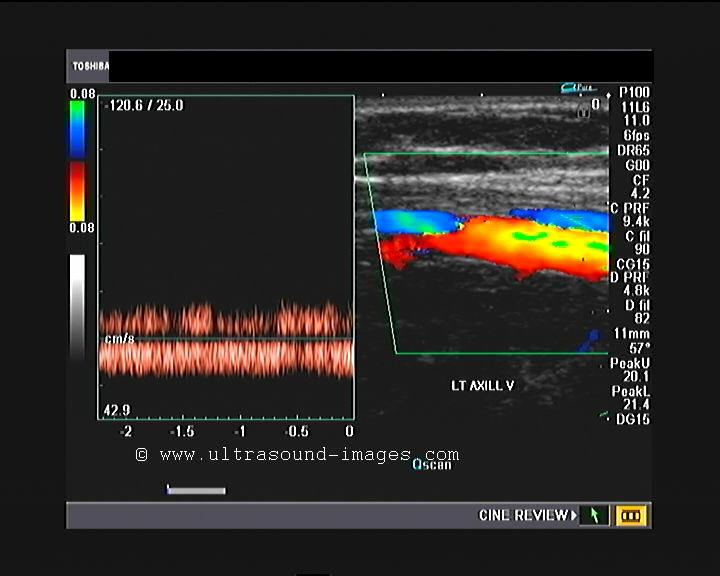

This young woman of 28 years age presented with pain and numbness of both upper limbs. colour Doppler ultrasound study of the left upper limb was done to evaluate the arterial system of this limb. All the arteries, starting from the left axillary artery, the left brachial artery, the left ulnar and radial arteries all show a tardus parvus pattern suggesting a high-level severe stenosis, possibly at the level of the left subclavian artery. all the arteries shown here show very low pulsatility and an almost venous flow pattern. Similar features can be expected in the arterial system of the right upper limb also. Such findings are typical of a condition known as Takayasu arteritis all a aorto-arteritis or pulse less disease. In Takayasu arteritis the common carotid artery as well as other major vessels may show extensive narrowing and stenosis due to wall thickening of a uniform nature. this ultrasound appearance is known as macaroni sign. Unlike atherosclerotic narrowing of the arteries, in Takayasu arteritis, there is uniform rather than segmental thickening of the arterial wall. Among the earliest and commonest sites of involvement, is the left subclavian artery and later the aorta, common carotid arteries as well as other major arteries.